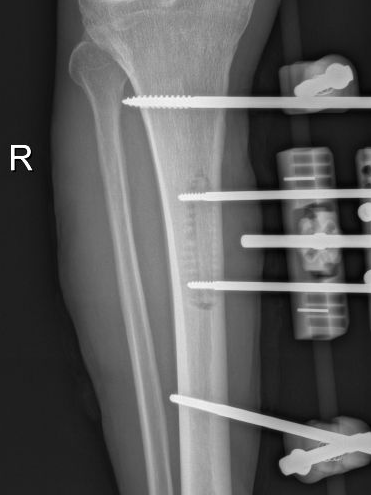

为提升区域内基层医疗机构糖尿病足诊疗服务能力、促进青年医师对糖尿病足的规范化诊治水平,遵义市第二城市医疗集团总院(贵州航天医院)圆满举办贵州省继续医学教育项目——胫骨横向骨搬移技术治疗糖尿病足专题研讨班。 贵州航天医院党委委员、副院长彭亮出席会议并致辞,遵义市第二城市医疗集团各成员单位,以及红花岗区、汇川区、绥阳县、桐梓县等多个区县的基层医疗机构骨干医师参加会议。 研讨班 本次研讨班以胫骨横向骨搬移技术在糖尿病足治疗中的应用为核心主题,围绕糖尿病药物治疗与生活方式管理策略、围手术期血糖精准调控要点、胫骨横向骨搬移技术典型病例深度解析、糖尿病足的临床分型与个体化治疗方案制定等临床实践中的热点与难点展开深入探讨,通过专题授课、案例研讨、互动交流等多元化形式,为参会者搭建了理论与实践结合的学习平台。 此次研讨班不仅为区域内基层医院搭建了学术交流与经验共享的平台,更对推动糖尿病足预防、诊断与治疗的规范化、系统化发展起到了积极作用,有效助力青年医师更新专业知识体系、提升临床技能,为进一步保障区域内糖尿病足患者的健康奠定了坚实基础。 贵州航天医院骨科专家简介 陈明勇 骨一科主任,副主任医师 临床擅长:从事创伤骨科工作约20年,对骨缺损、骨不连、骨肿瘤、肢体畸形等的肢体矫形重建及功能重建,慢性化脓性骨髓炎的根治治疗、糖尿病足的保肢治疗、快速康复理念(ERAS)下的老年骨折的诊治,四肢复杂骨折的诊治,四肢骨折等微创手术治疗具有丰富的临床经验。 2004年毕业于遵义医学院临床专业,曾在中国人民解放军总医院、广西医科大学第一附属医院、上海第六人民医院骨科进修。中国中西医结合学会骨伤科专业委员会横向骨搬移治疗糖尿病足及微血管网再生学组首届委员,遵义市医学会创伤分会常务委员。 瞿 晖 骨科党支部书记,骨二科主任,副主任医师 临床擅长:对骨科的常见病、关节外科、脊柱外科及运动医学疾病的诊治具有丰富的临床经验,熟练掌握骨科手术操作技术。 毕业于遵义医学院临床医学系,2005年前往广州中山大学第一附院骨显微医学部进修学习,2011年前往成都华西医院进修学习,并多次在省内外学习骨科相关知识,是中华医学会骨科分会会员。 赵小锋 中共党员,骨二科副主任,副主任医师 临床擅长:从事骨科临床工作11年,对骨科常见病、多发病诊疗有较为丰富的临床经验,擅长脊柱相关疾病诊断及治疗,尤其是颈、腰、腿疼痛疾病诊断及治疗,擅长胸腰椎骨折微创经皮穿刺内固定术、经皮穿刺椎体成形术、经皮穿刺脊柱内镜下腰椎间盘摘除术、单纯开创腰椎间盘摘除术、腰椎滑脱复位椎间植骨椎融合内固定术、腰椎管狭窄减压融合内固定术及人工髋、膝关节置换术等。 2012年毕业于遵义医学院外科学专业硕士研究生,2019年参加“遵义市115医学人才精英计划”于上海交通大学第一附属医院培训学习,2023年于北京大学第三人民医院脊柱外科进修学习,曾获得遵义市优秀医师荣誉称号。 遵义市手外科第一届委员,遵义市医学会创伤分会第一届委员,遵义市医学会创伤分会第二届委员,贵州省康复医学会第三届脊柱脊髓专业会委员,遵义市医学会烧伤与整形外科学分会委员,发表论文5篇,其中国家级核心期刊1篇,SCI论文1篇,主持市级课题1项并结题,参与市级课题2项。 赵兴东 骨科主任医师 临床擅长:擅长骨科的常见病及各种创伤、四肢骨折创伤修复、骨感染、手足疾病的诊治和手足体表畸形的矫形整复,熟练掌握骨科四肢骨病及创伤的手术操作技术,尤其在四肢关节复杂性损伤、手足外伤、组织缺损创面、难治创面的皮瓣修复方面及平足、高弓足矫形方面及四肢慢性疼痛诊治、康复方面具有丰富的临床经验。 硕士研究生,毕业于遵义医学院临床外科系,2015年前往山东省立医院手足外科进修学习;遵义市医学分会创伤分会第一、二届委员,遵义市手外科医学会第二委届员会常务委员;在省级及省级以上期刊发表文章9篇,参编著作2部,参与主持并完成市级课题1项,参与市级课题2项、省级课题1项。 张艳金 中共党员,骨科副主任医师 临床擅长:从事骨外科工作16年,对复合伤、多发伤的救治、四肢骨干骨折、关节周围骨折、骨肿瘤、骨髓炎等诊治具有丰富的临床经验。 中共党员,硕士研究生,2006年本科毕业于山西医科大学第二临床医学院,2011年研究生毕业于北京军区总医院;在“老年COPD患者合并髋部骨折的诊治”国际合作课题组研究两年,在老年髋部骨折的诊治方面具有丰富的经验,并发表论文6篇;主持遵义市级课题1项,承担遵义医科大学的临床教学工作,获得遵义医科大学优秀带教老师荣誉。编撰有《骨科疾病诊疗精粹》一书,开展2项新技术,编撰地方规范《务川自治县创伤骨科常见疾病诊疗规范》一书。 张俊凯 骨科副主任医师 临床擅长:从事骨科临床工作28年,对创伤骨折、骨感染、骨缺损、骨不连等外科诊治,四肢骨折的微创手术治疗,四肢复杂骨折(如关节内粉碎性骨折、多发骨折等)的损伤控制及手术治疗等具有丰富的临床经验。 1995年毕业于遵义医学院临床专业,2009年前往复旦大学附属医院骨科进修1年。 卢懿明 中共党员,骨科副主任医师 临床擅长:从事骨科工作18年,对创伤骨折、四肢骨折的微创手术治疗、四肢复杂骨折(如关节内粉碎性骨折、多发骨折等)的损伤控制及手术治疗,尤其是髋部骨折的PFNA等微创技术,踝关节骨折、膝关节周围骨折的Mipo微创技术等具有丰富的临床经验,开展了4项新技术,发明6项新型专利技术。 2005年毕业于遵义医学院临床专业,2017年,前往南方医科大学第三附属医院骨科进修半年,回院后运用Mipo技术对骨干骨折及干骺端骨折的治疗技术,同时积极开展骨盆骨折、髋臼骨折腹直肌外侧切口的应用;发表了多篇专业论文,经常参与省内外学术交流会授课,获得医院荣誉称号多个。 邬夏荣 骨科副主任医师 临床擅长:从事骨科工作16年,对四肢复杂骨折、骨肿瘤的诊治,尤其是足踝创伤、慢性踝关节损伤、平足症等诊疗具有丰富的临床经验。 2006年毕业于遵义医科大学临床医学专业,曾在陆军军医大学西南医院进修学习,发表多篇骨科学术论文。 余德怀 中共党员,骨科副主任医师 临床擅长:从事骨科工作10余年,对运动医学、骨关节、脊柱外科常见病、多发病的诊治具有丰富的临床经验。 硕士研究生,2011年毕业于遵义医学院临床医学专业,曾前往遵义医科大学附属医院运动医学专业进修学习;是贵州省医学会运动医学分会青年委员,西部关节镜联盟委员;发表多篇骨科学术论文。 冯 乾 骨科副主任医师 临床擅长:从事骨科工作近20年,熟练掌握骨科多发病及常见病的诊治,尤其对脊柱退变性疾病的诊断及治疗具有丰富的临床经验,主要研究脊柱微创相关治疗方式,能熟练开展椎间孔镜及UBE。 曾前往北京大学第三医院进修学习疼痛及椎间孔镜、首都医科大学友谊医院专业进修脊柱内镜;是贵州省康复医学会第三届脊柱脊髓专业委员会委员;发明专利3项、发表脊柱外科专业论文多篇。 贵州航天医院骨科简介 基本情况 贵州航天医院(原3417医院)骨科组建于1968年,前身是以创伤和断肢(断指)再植闻名于世的上海市第六人民医院骨科,中国断肢(断指)再植的奠基者、中科院院士陈仲伟等专家莅临科室指导医疗和教学,并在70年代开展了贵州省首例断肢(断指)再植手术。组建50余年来,诊治患者已逾百万,挽救了无数的伤病员,成为了保障遵义地区人民群众健康的重要支撑。 经过几代人的不懈努力,今天的骨科,已由创伤骨科发展至骨病、骨肿瘤、骨结核等领域,现有脊柱外科、关节外科、四肢创伤、手足外科四个亚专科,成为了集医疗、教学、科研于一体的综合学科,是贵州省临床重点专科、遵义市临床重点专科、遵义市骨科临床医学中心、遵义市基层骨科专科联盟理事长单位。 科室目前开放床位110张,共有医护人员50余人,副高级以上专家18人,硕士研究生15人。拥有一流骨科医疗设备多台,每年不定期选派优秀技术骨干到全国各大知名医学院校进修、学习、参观、交流,并邀请国内、国外知名专家教授来院进行交流、指导,通过不断引进国内外先进的诊疗技术,科室医疗技术水平稳步提升,为广大人民群众提供了优质的医疗服务。 专科特色 骨一科 (一)骨缺损、骨不连的肢体与功能重建 胫骨横向骨搬移技术治疗糖尿病足: (二)慢性骨髓炎的根治治疗 (三)肢体缺血性疾病如糖尿病足、脉管炎的保肢治疗 (四)皮瓣修复 (五)复杂创伤的治疗 (六)老年髋部骨折及小儿骨折快速手术 老年髋部骨折: 骨二科 (一)胸腰椎骨折微创经皮椎弓根螺钉固定术 (二)老年性骨质疏松性患者腰椎滑脱脊柱内固定术(骨水泥螺钉) (三)V形双通道脊柱内镜技术(VBE)腰椎融合术治疗腰椎退行性疾病 (四)老年性骨质疏松性骨折(PVP/PKP)术 (五)人工髋关节置换术 (六)双侧股骨头坏死人工全髋关节置换 (七)右侧全髋置换术后假体周围骨折翻修 (八)人工膝关节置换术 (九)人工膝关节假体松动翻修 (十)关节镜技术 传统手术切口 关节镜技术切口 诊疗范围 骨一科 1.四肢创伤、矫形。 2.手、足踝外科。 骨二科 End